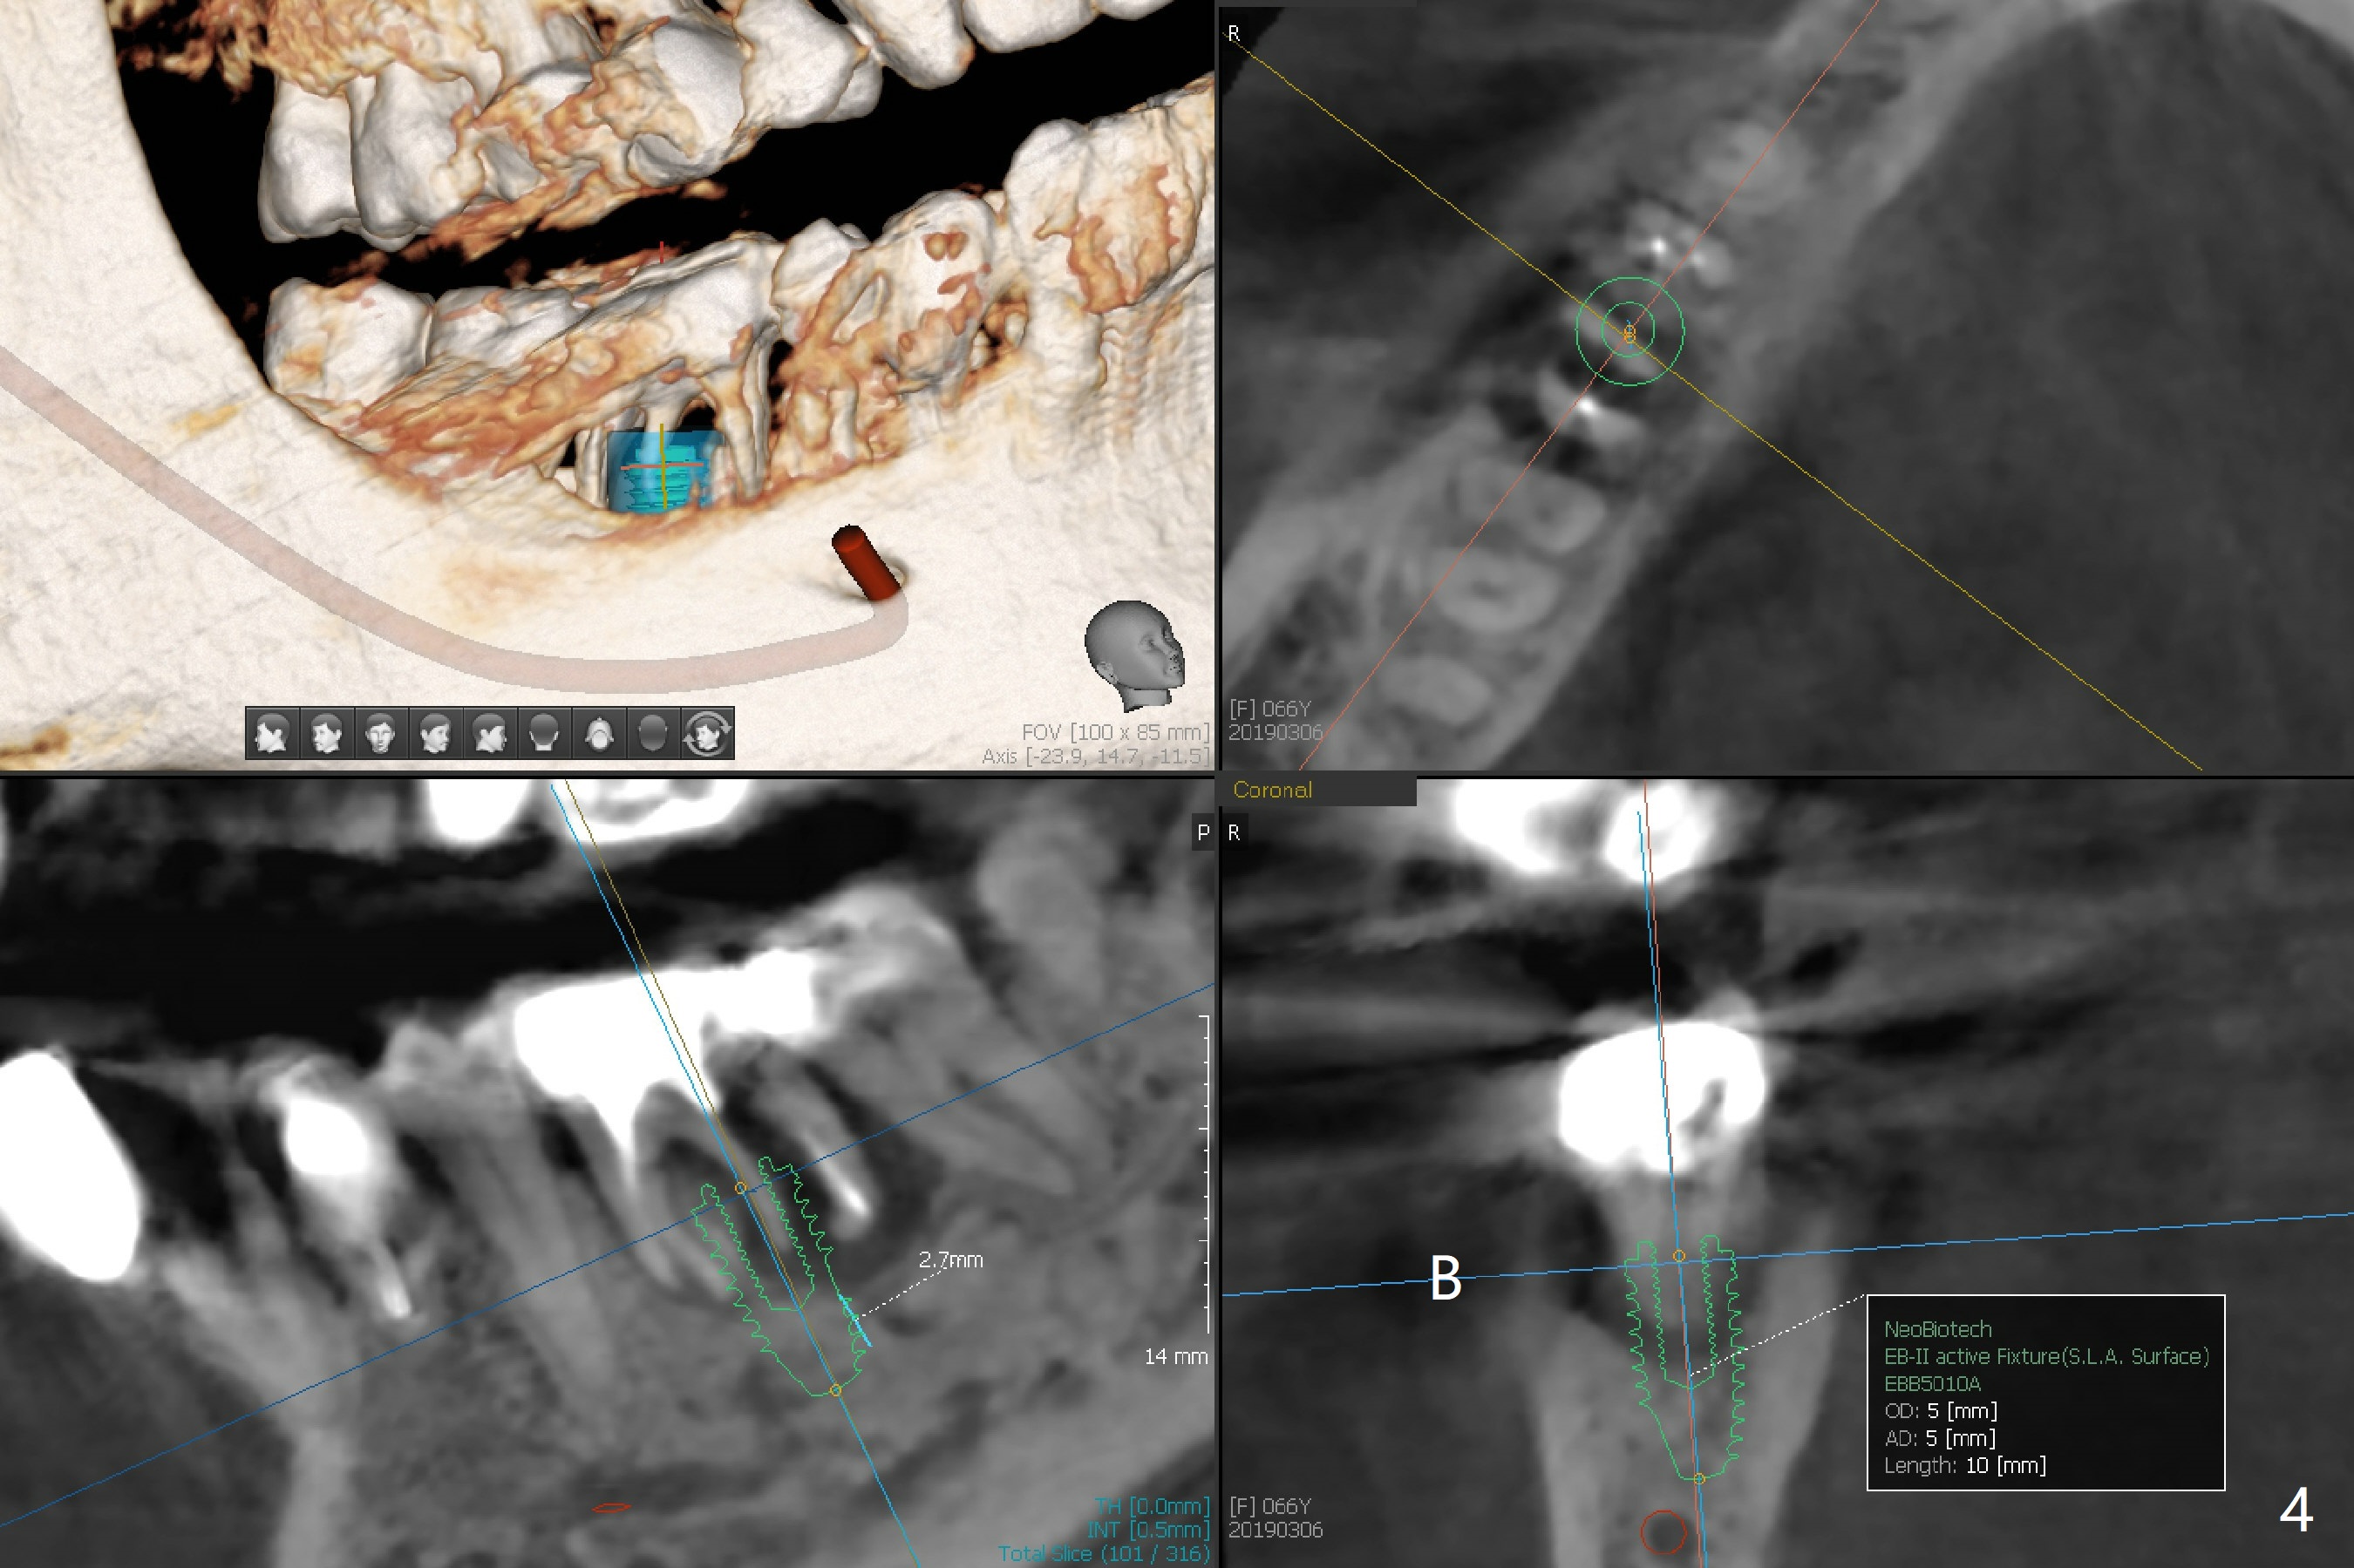

A 66-year-old woman loses a lot of bone at #30 in 4-5 months (Fig.1,2). There is severe buccal swelling, suggesting loss of the buccal plate and easy collapse of the gingiva after bone graft. In addition to an immediate provisional, periodontal dressing will be applied for support and seal. To prevent abutment screw loosening, guide will be used for implant placement in the most ideal trajectory (Fig.4). A tissue-level implant will provide with more security in prevention of screw loosening (Fig.5). If immediate implant is impossible, bone graft will be placed. Four months later, retake 5x5 cm CT for lab to determine the fitness of the guide.